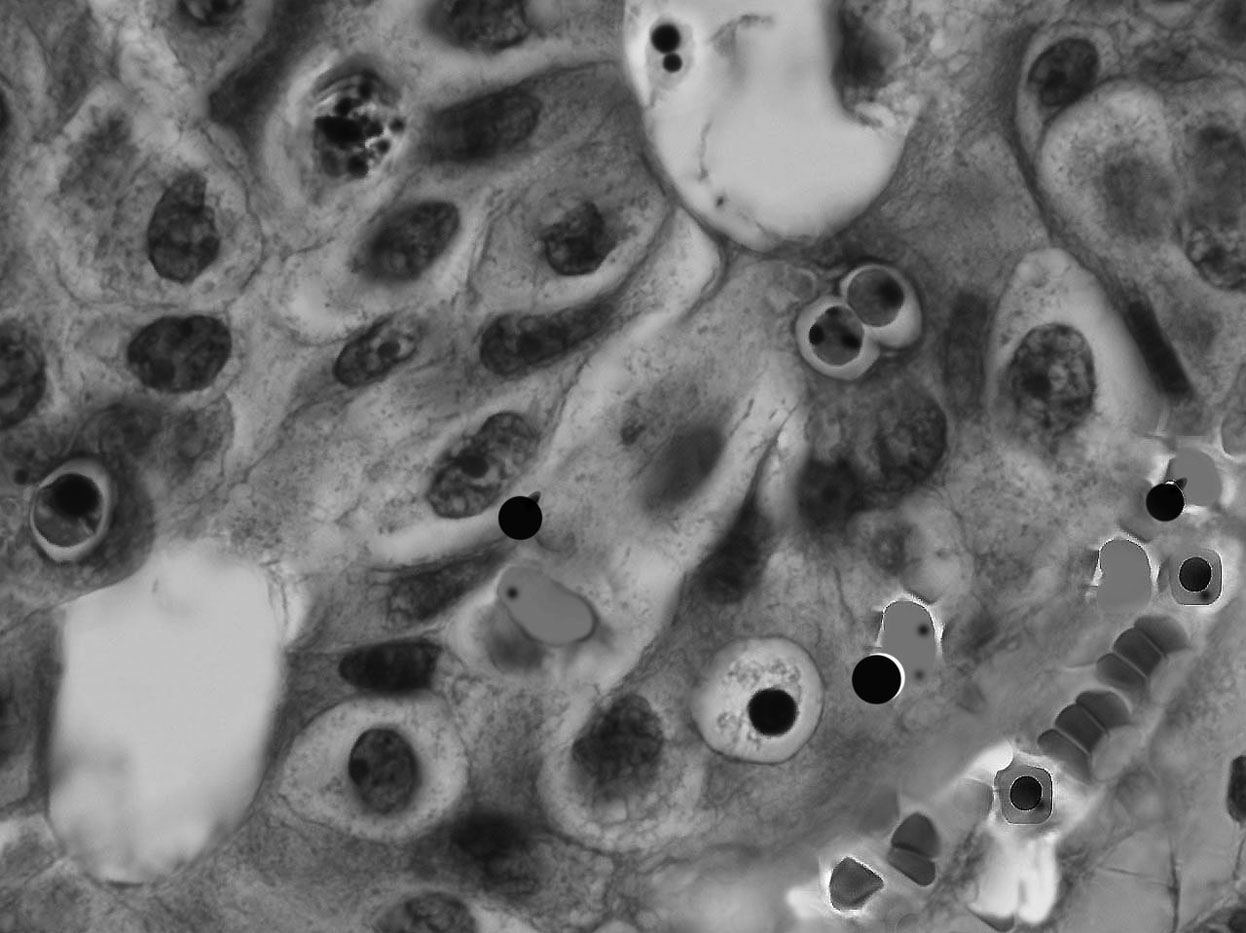

cancer-cells353604The dark side of seemingly miraculous immunotherapy cancer drugs.

Imagine you are diagnosed with melanoma, a cancer that can be quite deadly and compared to classical treatments such as chemo therapy which has a poor record for curing the disease, your doctor can get you into a clinical trial that gives you a greater chance of survival with a new type of treatment.

Immunotherapy is all the rage in cancer treatment circles, since it offers renewed optimism for a successful cure of a particular cancer.   Unfortunately, the promise of a cure sometimes comes with the side effect of the body attacking itself in ways researchers could not imagine.